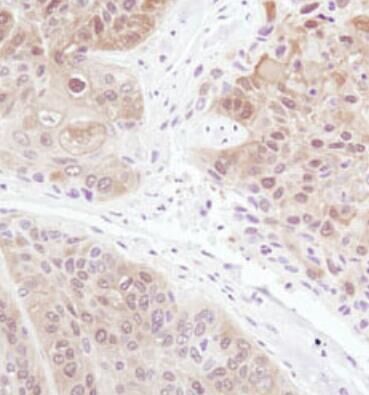

IHC 實驗操作(zuò)步驟 2020/3/18

參考抗體(tǐ)說明書選用(yòng)合适的抗體(tǐ)稀釋液和抗原修複處理(lǐ)方法。IHC方法:抗原修複緩沖液/抗體(tǐ)稀釋液...